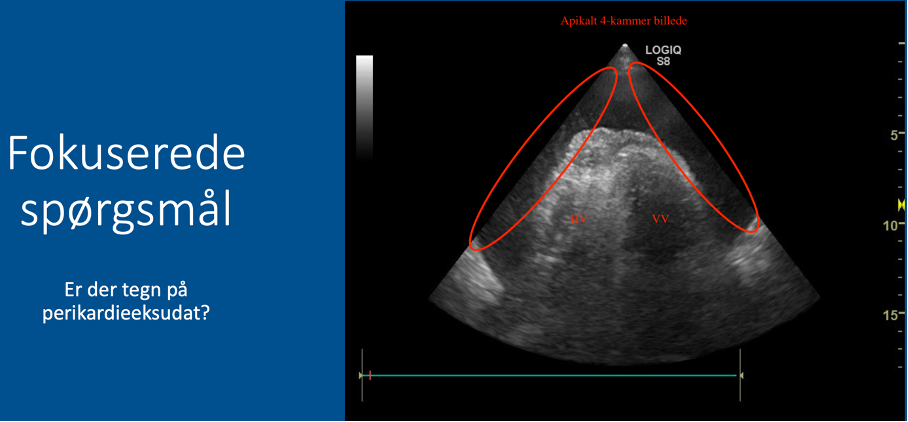

Fokuserede spørgsmål (FHUS):

* Perikardieeffusion: ja/nej?

11

* Tegn på højresidig belastning: ja/nej?

Vurder størrelsesforhold mellem højre og venstre ventrikel:

* Normalt forhold: VV (2/3) er omtrent dobbelt så stor som HV (1/3) –> INGEN tegn på højresidig belastning

* Abnormt forhold: hvis HV ≈ VV eller HV > VV –> tegn på højresidig belastning